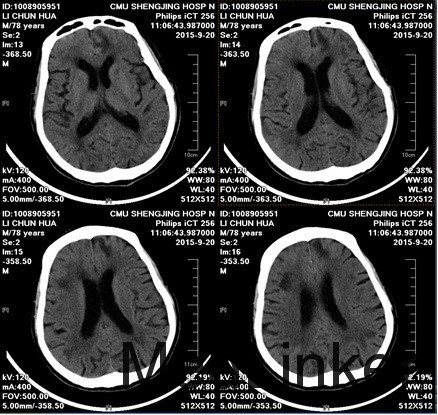

老年男性,78岁 主诉:以“头晕伴左侧肢体活动不利1天”为主诉入院。 现病史:2015/09/19 患者无明显诱因出现头晕伴左侧肢体活动不利,无恶心、呕吐,无视物旋转,无意识障碍,略有耳聋,无发热。未经系统治疗。 2015/09/20 患者上述症状反复发作,现为求系统诊治来诊我院门诊,门诊以“急性脑梗塞”为诊断收入病房。目前症见:头晕伴左侧肢体活动不利,神志淡漠,语笨,略有耳聋,时有咳嗽,咯少量黄痰,无恶心、呕吐,无胸闷、胸痛,无腹痛,无发热,饮食、睡眠尚可,二便正常。 既往史:2个月前余我院行前列腺增生手术,术后恢复尚可;否认糖尿病、高血压,冠心病病史;否认青光眼,白内障病史;否认肝炎结核传染病病史;否认外伤及输血史; 过敏史:否认食物药物过敏史。 辅助检查:1、心电图(本院,2015-09-20):窦性心律 ,P:68次/分,正常心电图; 2、头部CT:脑内多发梗塞及软化灶,脑白质疏松、脑萎缩;

诊断:脑淀粉样血管病;脑出血;蛛网膜下腔出血;脑梗塞; 患者入院给予营养神经,改善循环,抗血小板治疗,9月22日出现抽搐,9月23日发现患者蛛网膜下腔出血,停用改善循环,抗血小板药物,应用止血药,尼膜同口服,9月23日复查头CT,发现脑出血,予以营养神经、降颅压等治疗,患者病情平稳,症状逐渐好转中,10月13日,复查头CT,患者原有出血较前吸收,但右侧侧脑室后角旁新发脑出血,继续按脑出血治疗中。